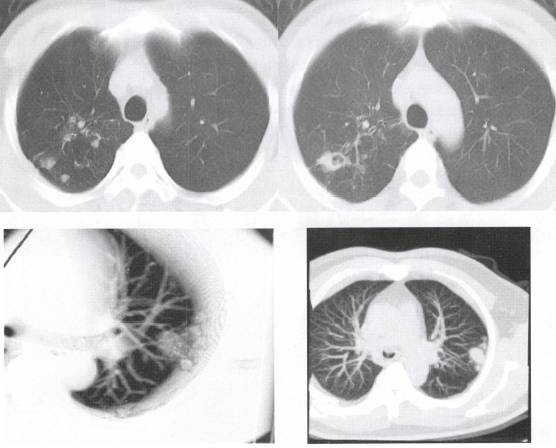

图1示右上肺病灶周围多发斑点状结节影及纤维条索状阴影

见图2。

图2肿块及空洞周围多发斑点状结节影 医学百科网 | YxBaike.Com

卫星灶其病理基础可能为结核结节周围播散灶及纤维增生灶,表现为无规律分布于结核球周围密度较高的斑点状或小条索状影,现普遍认为卫星灶是结核球的特征性表现,但要与炎性结节周围炎性反应形成的无规律分布的密度较淡的细小点片絮状影识别。

卫星灶对于判断结节阴影的良恶性性质上具有重要参考价值。卫星灶多见于肺结核球,周围型肺癌很少在肿块影周围出现卫星灶。 医学百科网 | YxBaike.Com